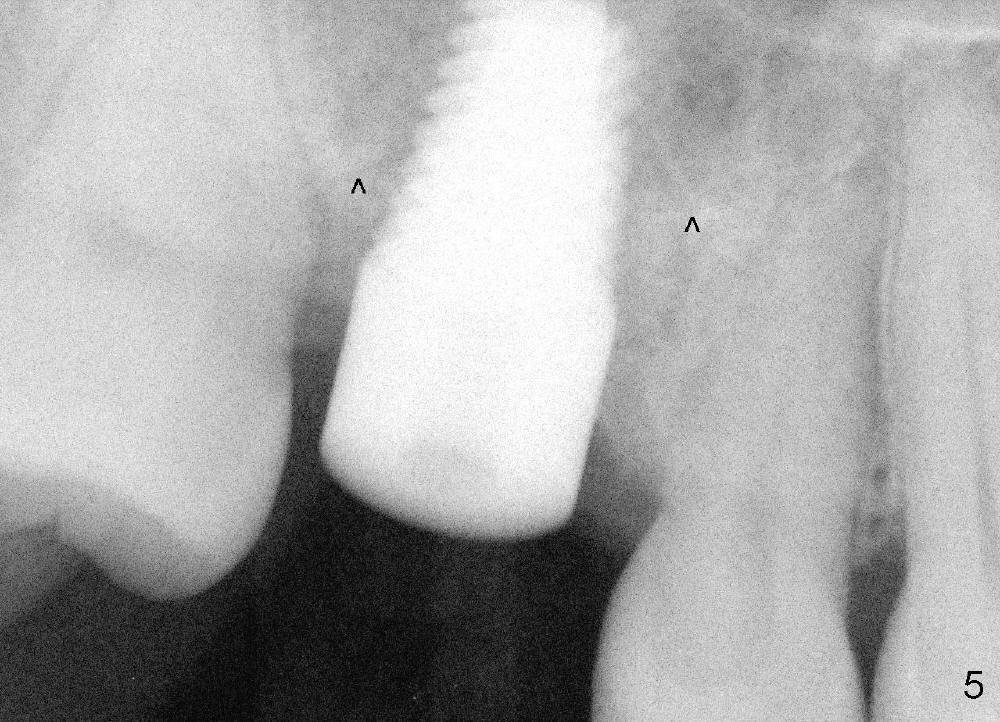

Our experience demonstrates higher failure rate associated with shorter implant in this situation. The depth of the osteotomy is then increased to 14 mm using the same series of osteotomes and taps. The bone at the top of the osteotomy finally wears off when the last tap is applied (7x17 mm). But the sinus membrane is intact. Osteogen is pushed into the osteotomy before placing a 7x14 mm implant with insertion torque > 60 Ncm (Fig.5). The implant contacts the gingiva tightly; no suture is necessary. There is no intra- or postop nasal hemorrhage. The wound heals 8 days postop (Fig.6). There is bone surrounding the apical portion of the implant in the sinus (Fig.7,8 *) 3.5 months postop. The implant is stable. There appears no crestal bone resorption 7.5 months post cementation (Fig.9 ^). Sinus lift is visible 16 months post cementation (Fig.10 (trimmed panoramic X-ray) arrowheads). There is discomfort between #2 and 3, probably due to poor oral hygiene. There is no deep pocket or bone loss (Fig.11, 26 months post cementation).